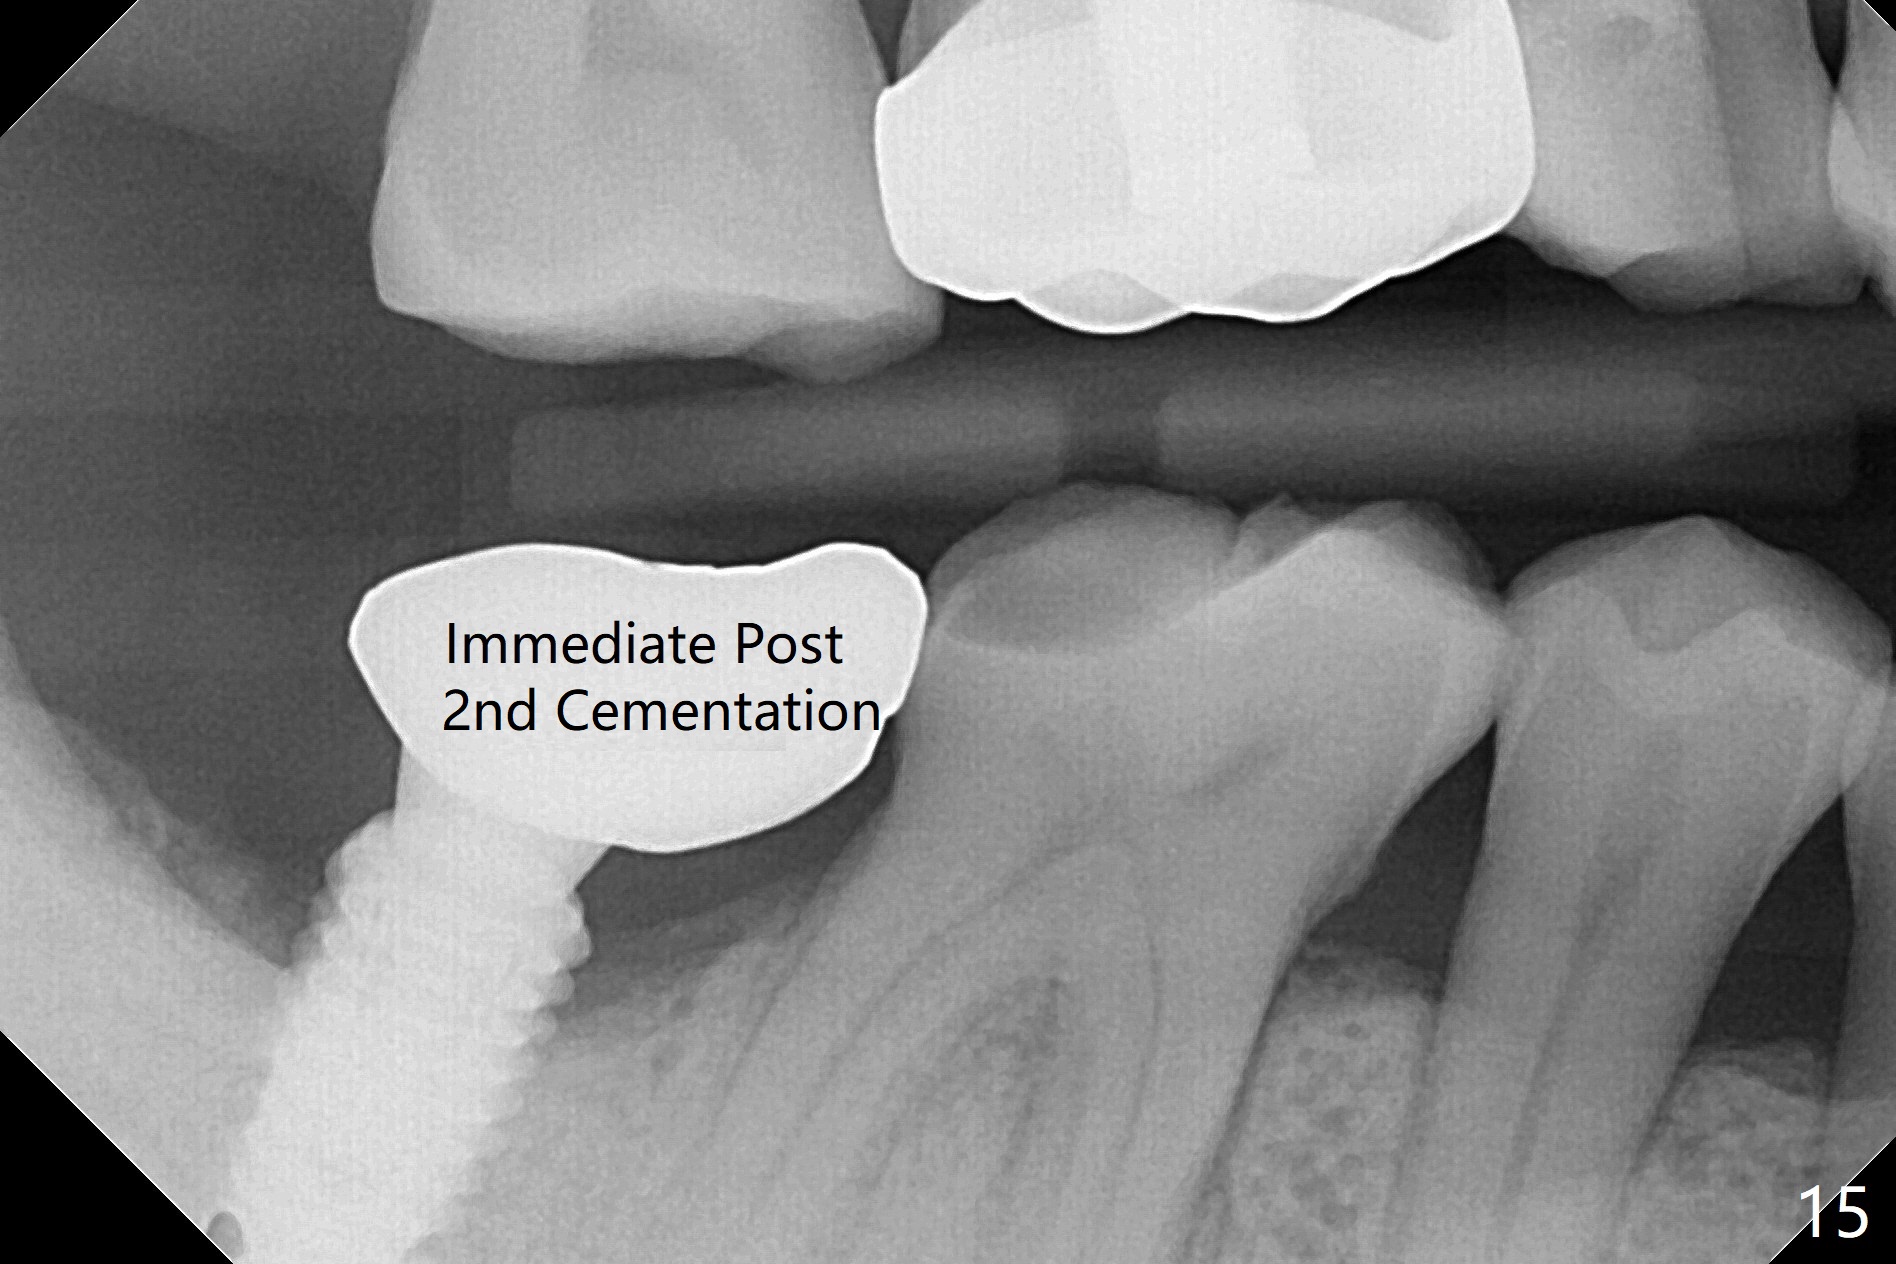

The residual roots of the tooth #31 are lower buccal (Fig.1 B), which in fact is molded and worn by the supraerupted tooth #2. When the tooth is extracted (Fig.2) and an implant, abutment (Fig.3 gold colored) and allograft (*) are placed, the abutment has to be trimmed. An atypical immediate provisional is fabricated by spreading setting acrylic over the abutment and bone graft (Fig.4 P) with occlusal equilibrium. Advantages of the guided surgery are good position (Fig.3 buccolingual), trajectory and depth (Fig.5,6) of the implant. The buccodistally exposed implant threads are packed with allograft in sufficient amount (Fig.3,5,6 *). The atypical immediate provisional breaks down and dislodges 3 weeks postop (Fig.7). In fact the implant plateau is exposed buccally. A monojet is given to the patient for self cleansing. He is instructed to return in 3 weeks. The exposed implant threads are covered 1.5 months postop (Fig.8). Incomplete abutment seating (Fig.9 <) was not noted until 1 year 3 month post cementation when the crown was mobile (Fig.10). A 6x3 mm healing abutment is placed. Three days later, the crown is sectioned and separated from the abutment. The latter returns to place; due to angulation associated with PA, the gap between the implant and abutment is indistinct (Fig.11). Bitewing is taken; the gap exists (Fig.12 <). The abutment seems to be seated deep; there is apparently soft tissue interference. A 5.2x4(2) mm abutment remains incompletely seated (Fig.13 >). A 5.2x4(3) mm one is completely seated (Fig.14 <). Zirconium crown with an access hole is cemented in the mouth. The crown and abutment is then removed for residual cement removal and reseated and torqued (Fig.15). Four months later, the Zirconium crown is fractured (Fig.16). Impression is retaken for high noble metal crown without access hole for strength (Fig.17).